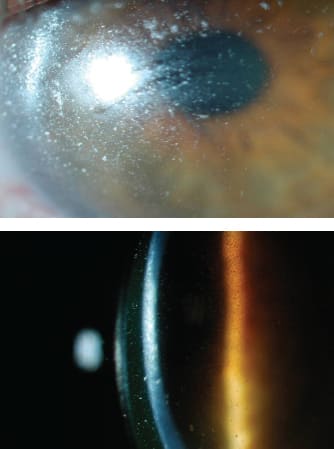

Patient #3 suffered from SJS for complained of dryness and light sensitivity. He had an asymmetric presentation of the condition (Figure 6), which is not that uncommon in limbal stem cell deficiencies. The patient's entering best-corrected visual acuity was hand motion OD and 20/50 OS. Optimizing the comfort for both eyes was crucial, but improving the vision in the left eye was a high priority as well. His vision subjectively improved in the right eye, and he achieved 20/25 OS with a scleral lens.

Figure 6. Patient #3, who has a history of SJS from more than 30 years ago. OD demonstrates diffuse pannus across the cornea with a paracentral anterior fibrotic scar (left photo). Superior pannus that spares the pupil OS appears in the right photo.

A symblepharon that is too close to the limbus may disqualify an eye or patient from scleral lens candidacy. Patient #4 had a history of SJS. Her right temporal symblepharon began to encroach onto the cornea. Multiple attempts to refit to smaller lenses proved uncomfortable and time-consuming. Her lens was notched to accommodate the symblepharon (Figure 7, left), but the tissue continued to advance. The patient underwent a symblepharon lysis with mitomycin C, but a new inferior temporal symblepharon developed (Figure 7, right). When encountering symblephara, it is important to ensure that there is room for the lens to settle. Fitting inside of a symblepharon reduces the risk of scleral lens impingement. Prolonged impingement could lead to conjunctival hypertrophy in normal tissue, and the symblepharon may react more aggressively.

Figure 7. Patient #4 had an advancing temporal symblepharon that required a notch to accommodate in the left photo. The right photo shows that after symblepharon lysis, the tissue is avascular where the symblepharon once was, but a new symblepharon formed.